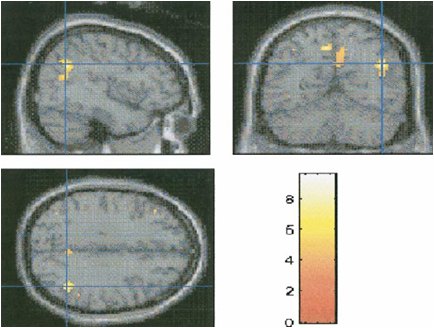

Bartels & Zeki, 2004: (a,b) Różnice aktywacji przy oglądaniu własnego dziecka względem innych znajomych dzieci.

(c) Różnice aktywacji przy oglądaniu własnego dziecka dorosłych przyjaciół.

aC =anterior cingulate cortex; aCv = ventral aC; C = caudate nucleus; F = frontal eye fields; Fu = fusiform cortex; I = insula; LPF = (ventral) lateral prefrontal cortex; occ = occipital cortex; OF = orbito-frontal cortex; Tha = thalamus; S = striatum (consisting of putamen, caudate nucleus, globus pallidus); PAG = periaqueductal (central) gray; SN = substantia nigra.